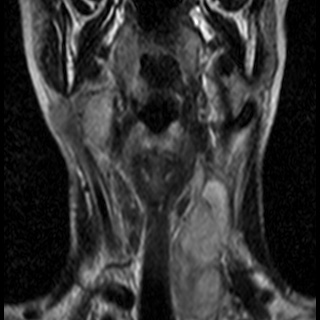

Невринома множественная шейного отдела с врастанием в спинно-мозговой канал

Здравствуйте! Мне 27 лет. Я стала жаловаться на головокружение, головные боли, пульсирование в голове. После исследования мрт выявилась следующая патология . Документы предоставляю. Можете ли Вы помочь в этой патологии? Как попасть к Вам на консультацию, учитывая эпидемиологическую обстановку? Спасибо.